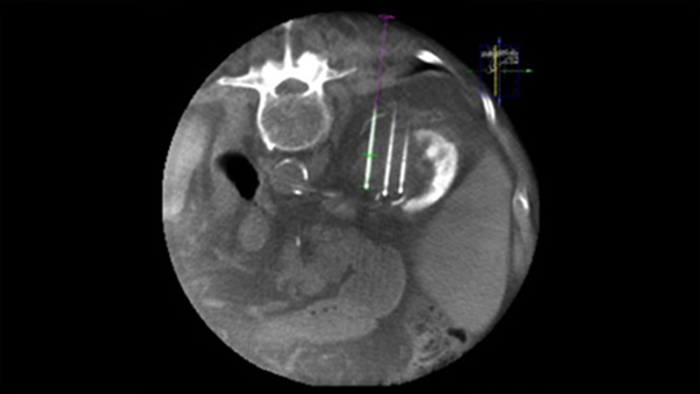

Heterogene Läsionen und fehlende Erkennbarkeit beeinträchtigen die Qualität von Proben sowie die Durchführbarkeit von Biopsien mithilfe von Ultraschall oder der klassischen CT. Da Lungenscreening-Programme immer gängiger werden, werden frühe Lungenkarzinome in Form von kleinen Rundherden inzwischen öfter entdeckt als je zuvor. Bei 14,5 % einer gescreenten Population wurden Rundherde ≤ 10 mm beobachtet.1-2 Unsere Nadelnavigationstechnologie mit CBCT erhöht die Präzision und ermöglicht das Targeting kleinerer (<= 1 cm) oder heterogener Läsionen mit größerer Genauigkeit und weniger Neupositionierungen der Nadel. Gleichzeitig kann die Strahlungsbelastung im Vergleich zur klassischen CT reduziert werden.1-2

Die perkutane Ablation (Hochfrequenz-, Mikrowellen- und Kryoablation) ist eine etablierte, minimal-invasive Behandlungsmethode für Nieren-, Leber-, Lungen- und Knochentumore. Dabei ist es besonders wichtig, den Tumor abzugrenzen und eine geeignete Anzahl an Nadeln und notwendigen Nadelverläufen festzulegen, damit der gesamte Tumor behandelt werden kann, ohne das umliegende Gewebe zu schädigen. Durch die präzise Navigation zur relevanten Läsion bei niedriger Strahlendosis und ohne Neupositionierung der Nadel werden die Erfolgschancen erhöht und das Komplikationsrisiko bei Biopsien und Ablationen reduziert. Der Endpunkt der Ablationsbehandlung kann mittels 3D-Bildgebung verifiziert werden, während sich der Patient noch auf dem Tisch befindet.

XperGuide bietet eine besonders präzise Live-Bildführung für jede Nadel zur Zielposition. Hierfür wird das Durchleuchtungsbild mit den vorab geplanten Bewegungsverläufen überlagert.3